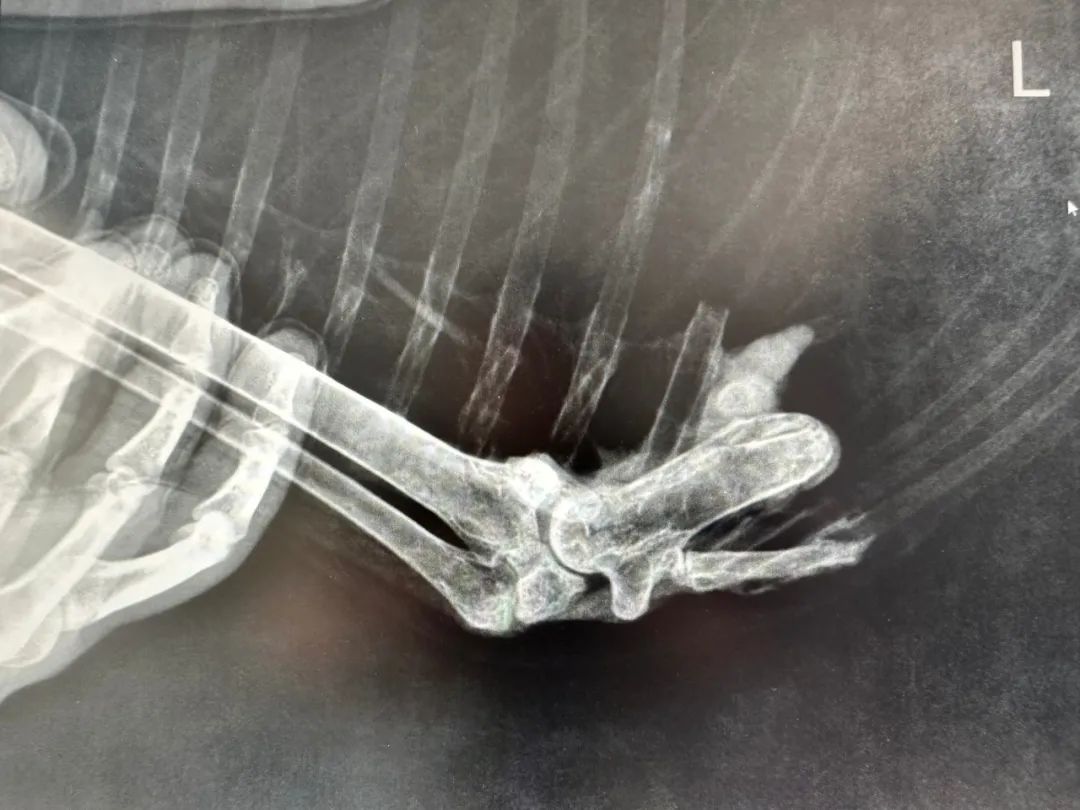

蓝天白云正是秋高气爽时,有朝一日小白可以展翅翱翔。当然,这一幕是众所期待的,汪湜决定带她去安庆骨科医院给受伤的翅膀拍张X光片,于是乎,小白的历险记也将被开启……

9时40分,目的地终于到了。小白下车后,站在医院的大厅里,她舒展了双翼,抖了抖身子,很快便用长长的喙开始梳理起羽毛来。说实话,她也挺有包袱的,很注意自己的形象。在志愿者和医护人员的共同帮助下,小白非常配合地完成了左边翅膀X光片的拍摄。院长说她受伤部位除有骨质增生外,没有发现其他异常,不太会影响她在自然状态下生活。